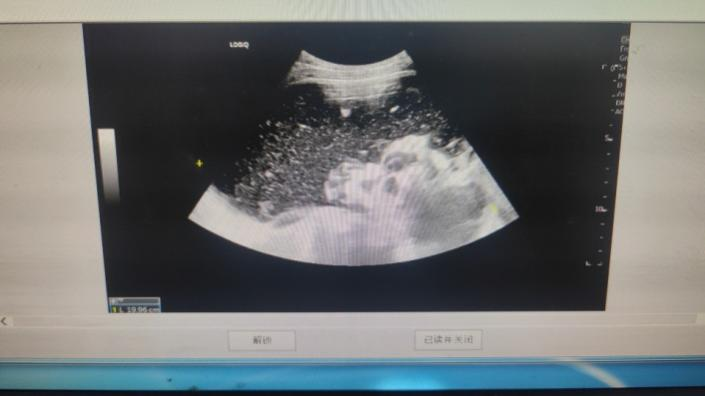

后说道:"患者存在左侧卵巢内混合回声,首先考虑黄体囊肿伴破裂出血

卵巢左侧囊肿

行b超检查显示右侧附件区见19.9×17.4×10